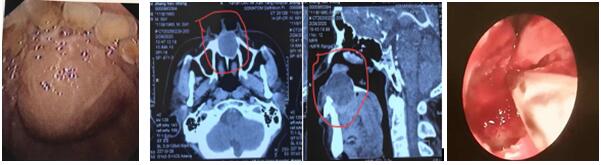

患者,男,59歲,因“發現口腔內腫物3月”入院,腫物累及鼻底,并導致鼻底嚴重隆起,經上頜骨CT三維重建檢查,腫物大,且口內粘膜因腫物壓迫已很菲薄,還合并腎病綜合癥,口服激素一年余。住院后張立剛主任組織術前討論,認為患者如行傳統經唇齦切口手術方式,極易導致傷口感染或不愈合,引起囗腔鼻腔漏,給患者帶來災難性后果。經查閱文獻,結合自身堅實的鼻內鏡技術基礎,決定行經鼻內鏡鼻底上頜骨囊腫摘除術。手術取鼻底小切口入路,切開黏膜后即見大量粘液溢出,清理后見口腔面黏膜菲薄,透光,與術前評估一致,遂將囊腫切除,等離子徹底止血,為防止壓迫導致口腔鼻腔漏形成,摒棄傳統的碘仿紗條壓迫兩周的觀念,術腔僅填塞可吸收明膠海棉,避免因填塞導致術后劇烈頭痛等不適。術后檢查見鼻腔結構完整,口內包塊明顯縮小,鼻面部無任何不適。

上頜骨囊腫在臨床上并不罕見,其發病隱弊,多無癥狀,當發現上頜骨囊腫時,其上頜骨破壞程度已相當嚴重。傳統手術方式創傷大,上頜骨骨質暴露多,術后出現頭痛、流淚、面部腫脹及麻木,易增加感染機會。